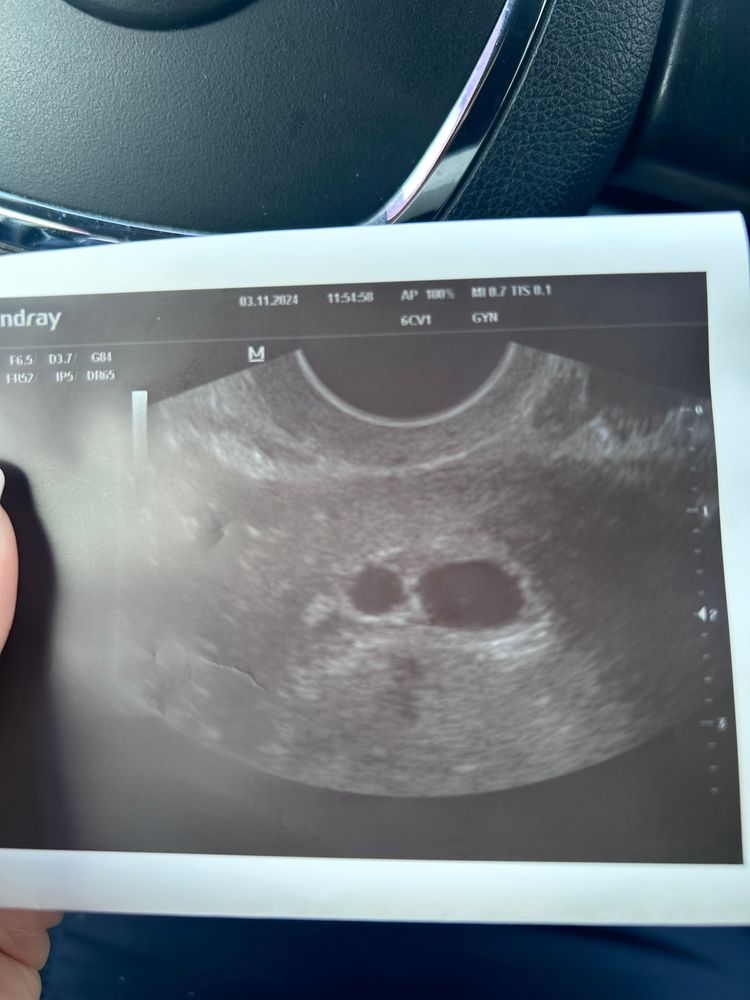

Девочки, сегодня была на первом узи. И так…. Прикрепилось 2 плодных яйца) Все же у меня двойня. Но…. В одном плодном яйце увидели желточный мешочек, в другом четко не увидели. Назначили контроль узи через неделю. Так что хгч и правда никому и ничего не должен))

Hopefullymom, спасибо большое. У Вас сразу 2 желточных мешочка увидели ? Переживаю, что в одном не увидели. Там вообще было такое ощущение, что во втором плодном яйце шарик светлый такой. Если на фото приглядеться, то видны очертания. Она сказала, что не знает, что это такое

Счастливая по жизни , не сказала. Сказала, что побольше которое, то вроде 7 мм. Она и заключение пока писать не стала. Сказала, что поменьше там желточный мешочек и всё как по книжке. Побольше четко не видит желточный мешочек. Придти через неделю и станет все понятно. Надеюсь, что у через неделю увижу 2 сердцебиения. А про хгч мне все писали, что хгч точно не для двойни 😁 но я еще по хгч с сыном поняла, что у меня хгч растет своеобразно))